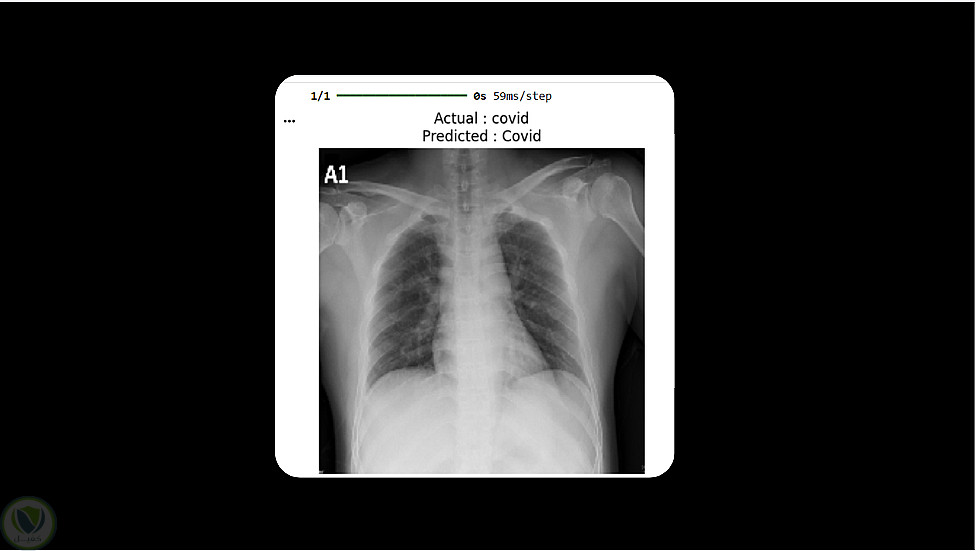

برنامج لتوقع الاصابة بمرض كورونا

قمت باستخدام احدي ادوات التعلم العميق بتدريب نموذج يساعد في التنبؤ بالفايروس